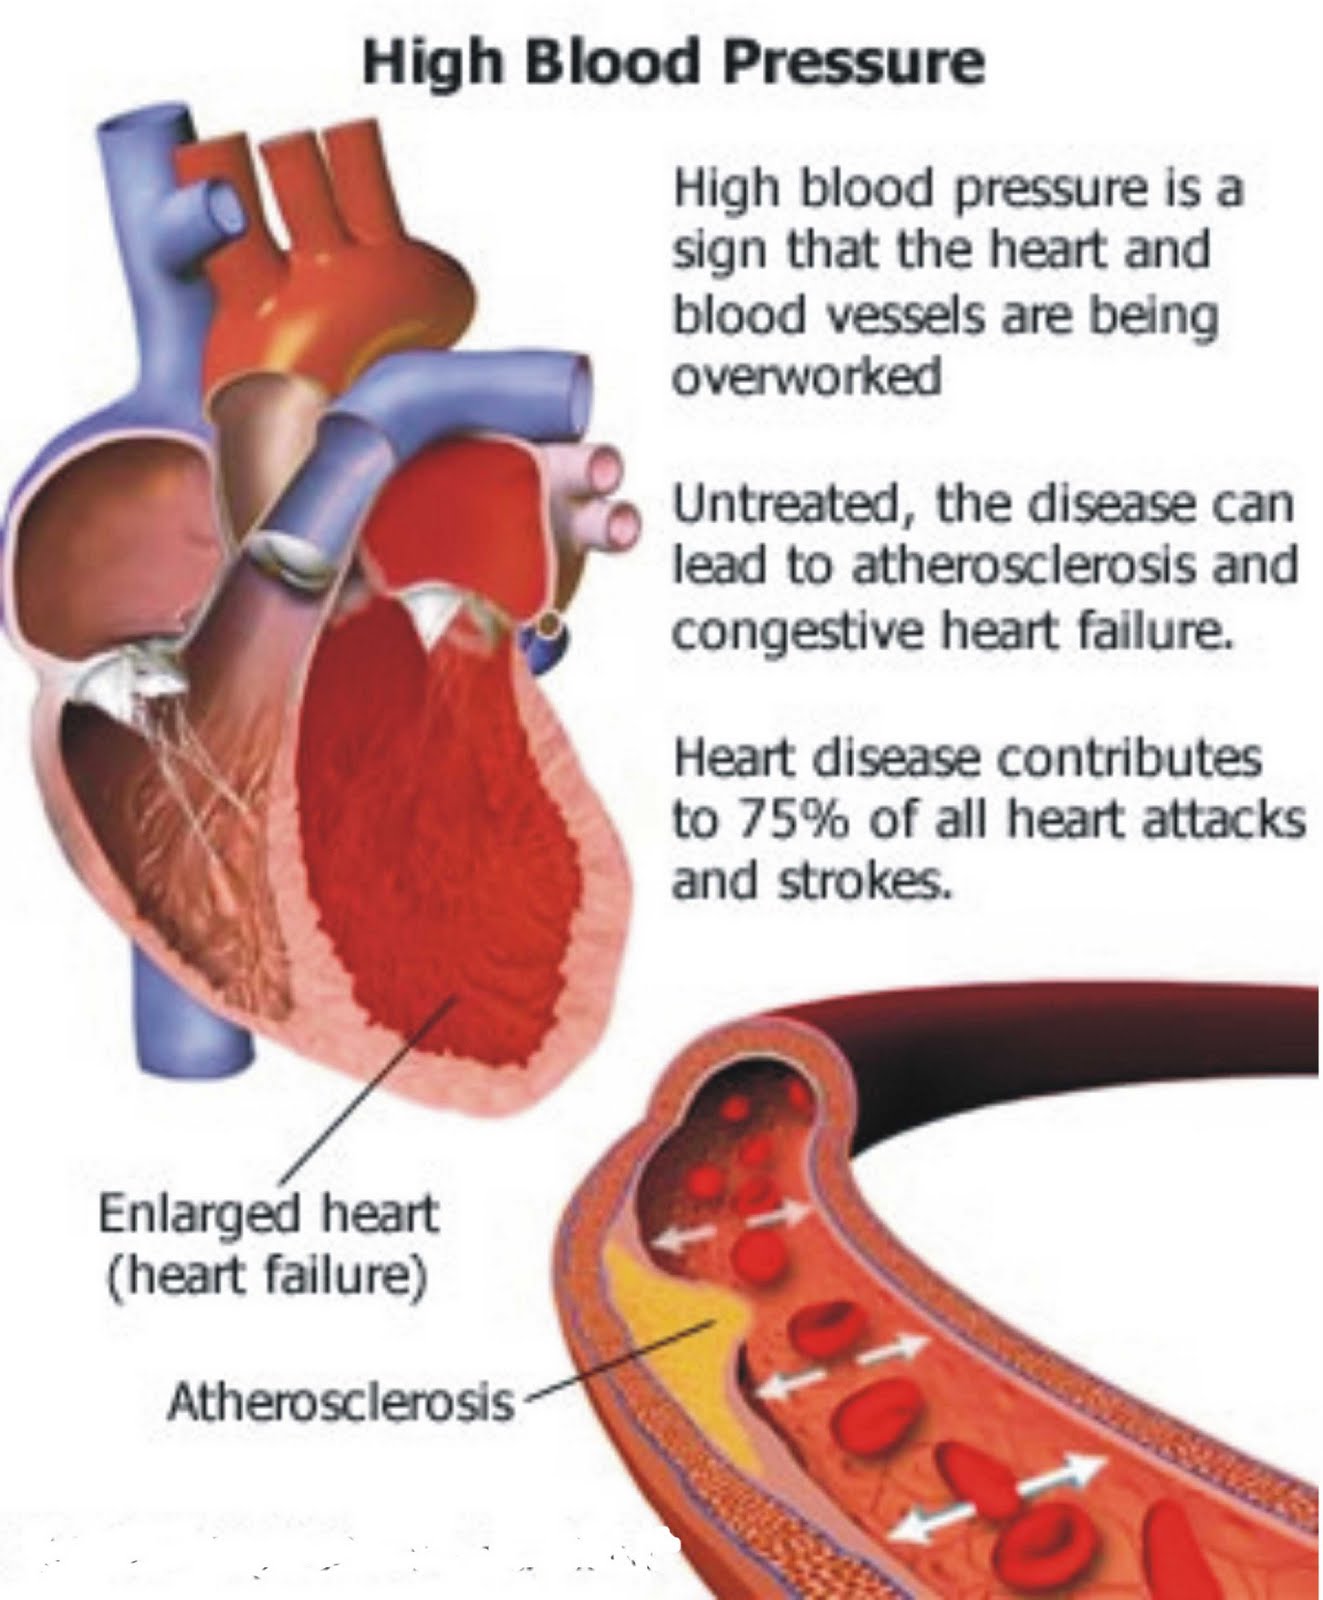

Arteriosclerosis / atherosclerosis – Symptoms and causes – Mayo Clinic

Atherosclerosis, also known as “hardening of the arteries,” is a …

ELIMINATE HIGH BLOOD PRESSURE